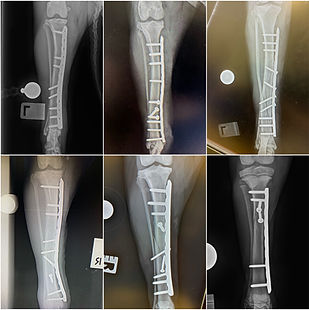

Fracture Clinic

Following immediate first-aid and stabilisation, get in touch with us to discuss repair options. Each case requires individual assessment. Once the patient is stable, many injuries are amenable to treatment in the outpatient setting, meaning more time at home and earlier return to function.

We'll help you get your pet back up and running after a serious injury.